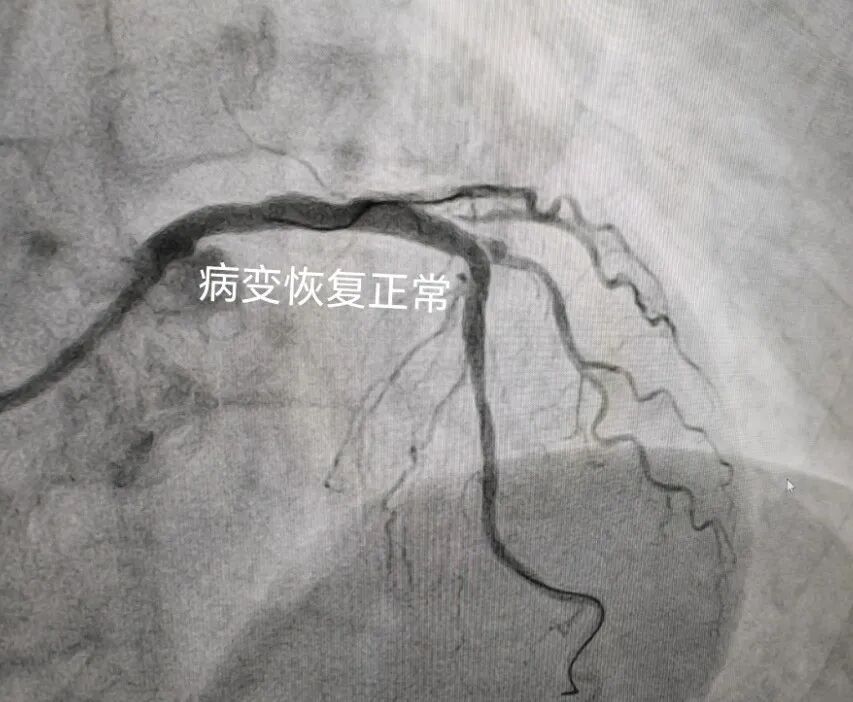

张阿姨在心病科住院后,心病科主任李爱勇为张阿姨辨证应用中药汤剂,组织科室团队充分讨论病情并制定个体化介入手术方案,经过心病科介入团队前期的充分准备,手术进展的十分顺利。术后张阿姨恢复较好,已康复出院。

冠状动脉左主干病变是指冠状动脉造影显示左主干直径狭窄程度≥50%的病变,约占总冠状动脉病变的2.5%~10.0%。左主干为大约75%的左心室心肌供血,左主干病变与巨大缺血风险相关,因此未治疗的左主干病变预后较差,长期以来一直是冠状动脉旁路移植术的专属领域,也是经皮冠状动脉介入治疗的“圣杯”,左主干病变血运重建没有一种“一刀切”的方法。北京中医医院内蒙古医院心病科团队综合考虑临床因素、解剖因素和患者本人意愿,为患者量身定制治疗策略。